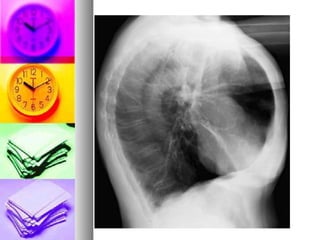

 Imagerie thoracique

 Rx thorax (F/P):

- Peu sensible et peu spécifique

- Cherche éventuellement les comorbidités

(cancer bronchique ,pneumopathie, cardiopathies)

-   Peut montrer des signes de distension

    Rx thorax (F/P) signes distension :

-   un aplatissement des coupoles

diaphragmatiques

-   une horizontalisation des cotes, une

hyperclarté

-   un cœur en goutte (Le coeur est petit,

allongé,se décolle de la coupole)

   Rx thorax (P) signes distension :

-   une ↑ de l’espace clair retrosternal et

retrocardiaque (profil)

-   une ↑ diamètre thoracique

ANT/POST(profil)